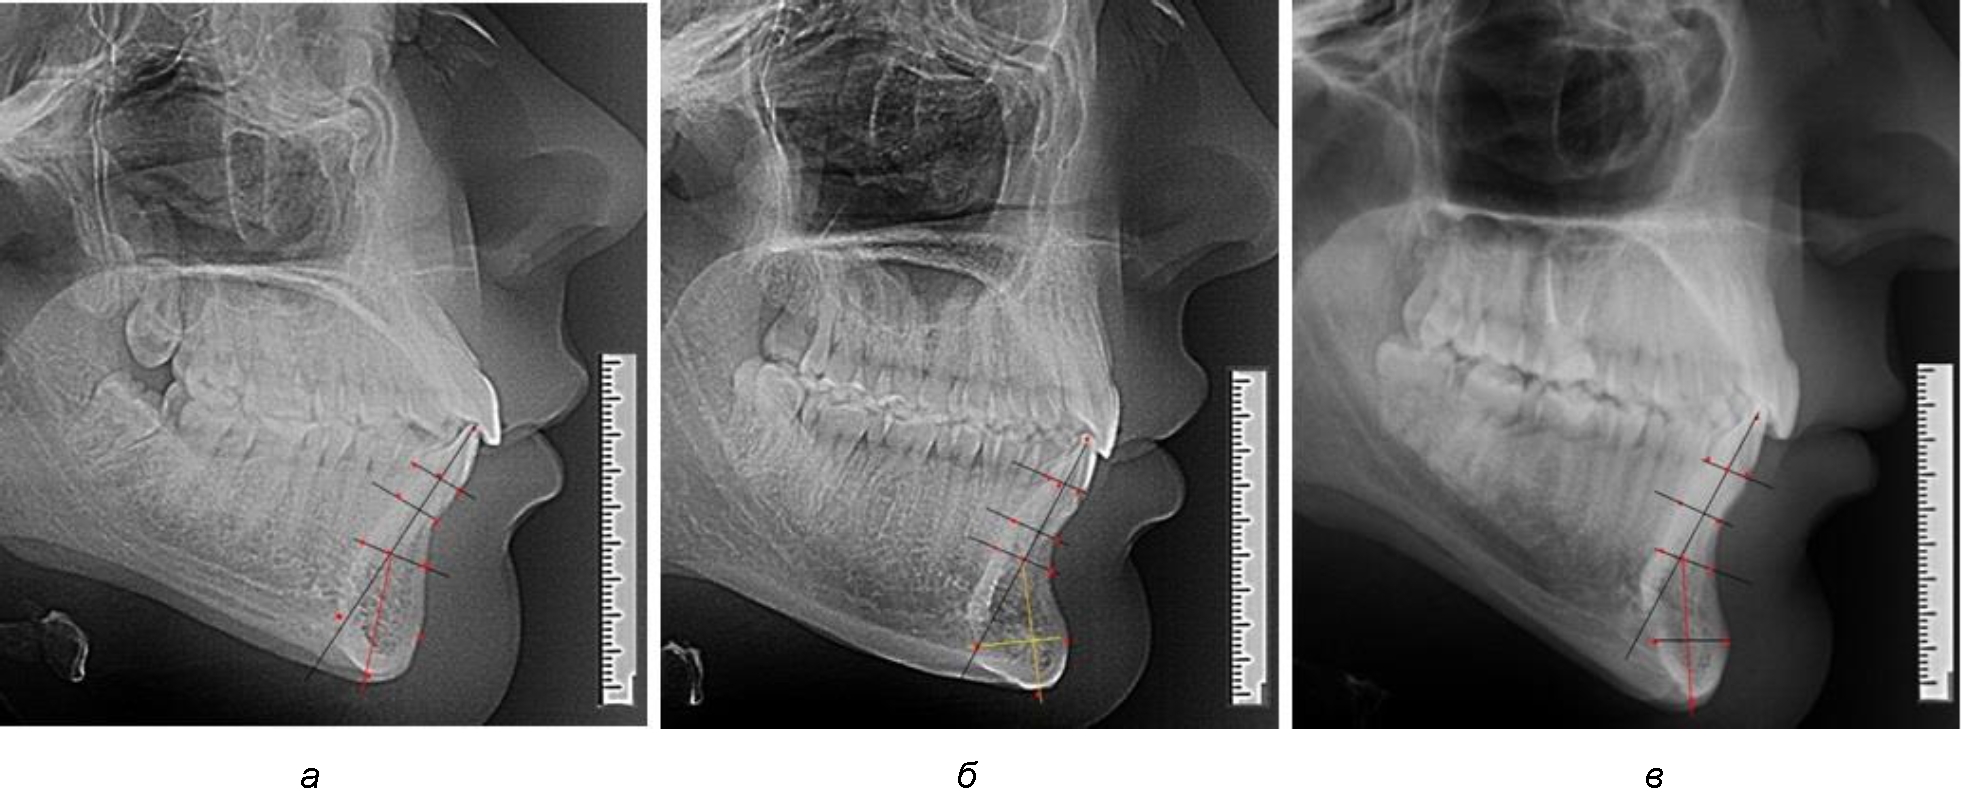

При анализе боковых телерентгенограмм использовали фрагменты гнатической части, на которых оценивали вертикальные и сагиттальные параметры резцового нижнечелюстного сегмента, на который наносили те же ориентиры, что и при анализе нативных препаратов и их рентгенограмм.

При необходимости и/или возможности проведения КЛКТ-исследования проводили анализ с сопоставлением фрагмента, что повышало точность диагностических мероприятий (рис. 2).

Рис. 2. Фрагменты ТРГ с ориентирами для измерения параметров резцового сегмента (а) и с наложением фрагмента КЛКТ (б)

Варианты резцовых сегментов нижней челюсти различные как по ширине, так и по высоте, а также по расхождению положения апикальных точек по Downs и Schwarz представлены на рис. 4.

Рис. 4. Особенности нижнечелюстного резцового сегмента на ТРГ у людей при среднем (а), широком (б) и узком (в) вариантах